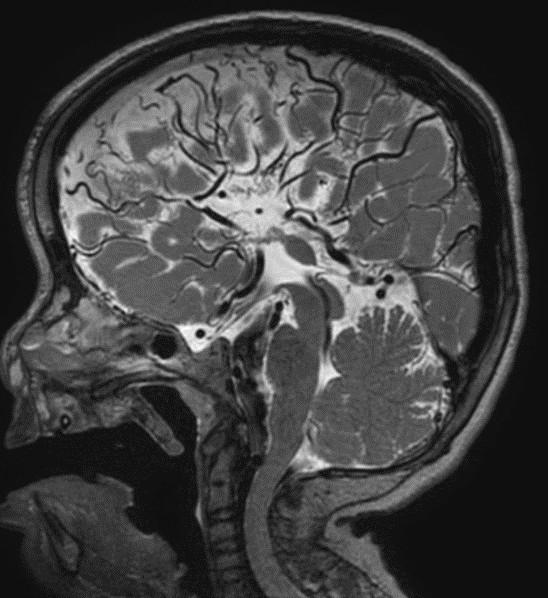

Sweep the Midline…Name the parts…where do we start?

Sag T2 Cube nongated Normal

Normal

Sag T2 Cube

Nongated: CSF dephasing in the aqueduct on this sequence

Primary fissure 3 lobes Closed fastigial point

Sag T2 Cube Normal

Anterior commissure

Corpus Callosum

Rostrum, genu, body, splenium

Sella/Suprasella

ON, post pit bright spot, stalk

Midbrain

Patent aqueduct

Pons

“just right…”

Vermis

3 lobes

Cerebellar Tonsils